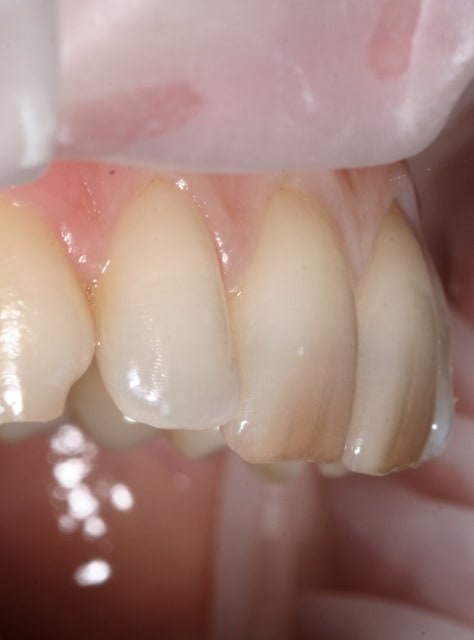

Patiente de 25 ans, le genre qui montrait plus un seul bout de dent même si elle avait envie de sourire...

L'hygiène a fait l'objet d'un topo et d'un accord clair : si c'était pas impeccable, fin de soins.

Elle ressourit avec ses compos :)

Comme l'a dit Sethef, c'est bien l'isolation des cavités qui pose le plus de problème...

- Détartrages dans les premières séances associés à technique de keyes 15jours pour retrouver une gencive non-inflammatoire.

- Curetage complet sous anesthésie et biseau périphérique au niveau de l'émail.

- Digue posée sur plusieurs dents mais composite réalisé dent par dent en décalant le clamp à chaque fois.

Effectivement, j'ai toujours peur du devenir de ces compos et surtout de l'inflammation gingivale qu'on peut retrouver si la finition n'est pas top.

Le polissage est réalisé avec fraises diamantées rouges puis jaunes puis meulette silicone CA.

Les limites sont vérifiées à la sonde. Je me satisfais quand elle ne raccroche plus aucune des limites.

Comme toi, sans complexe pour le polissage, ça saigne mais comme le résultat est meilleur la semaine suivante et plus durable...

Ca a été plus compliqué pour la 13, carie trop sous-gingivale pour correctement isoler... Hémostase au bistouri électrique, pose d'un CVI en excès, puis retouche du profil d'émergence à la fraise.

Composite de recouvrement la séance suivante, en repréparant dans le CVI pour coller sur de l'émail en mésial, distal et occlusal.

Le niveau gingival a baissé légèrement ensuite, puis s'est stabilisé, on distingue le CVI sur la photo.